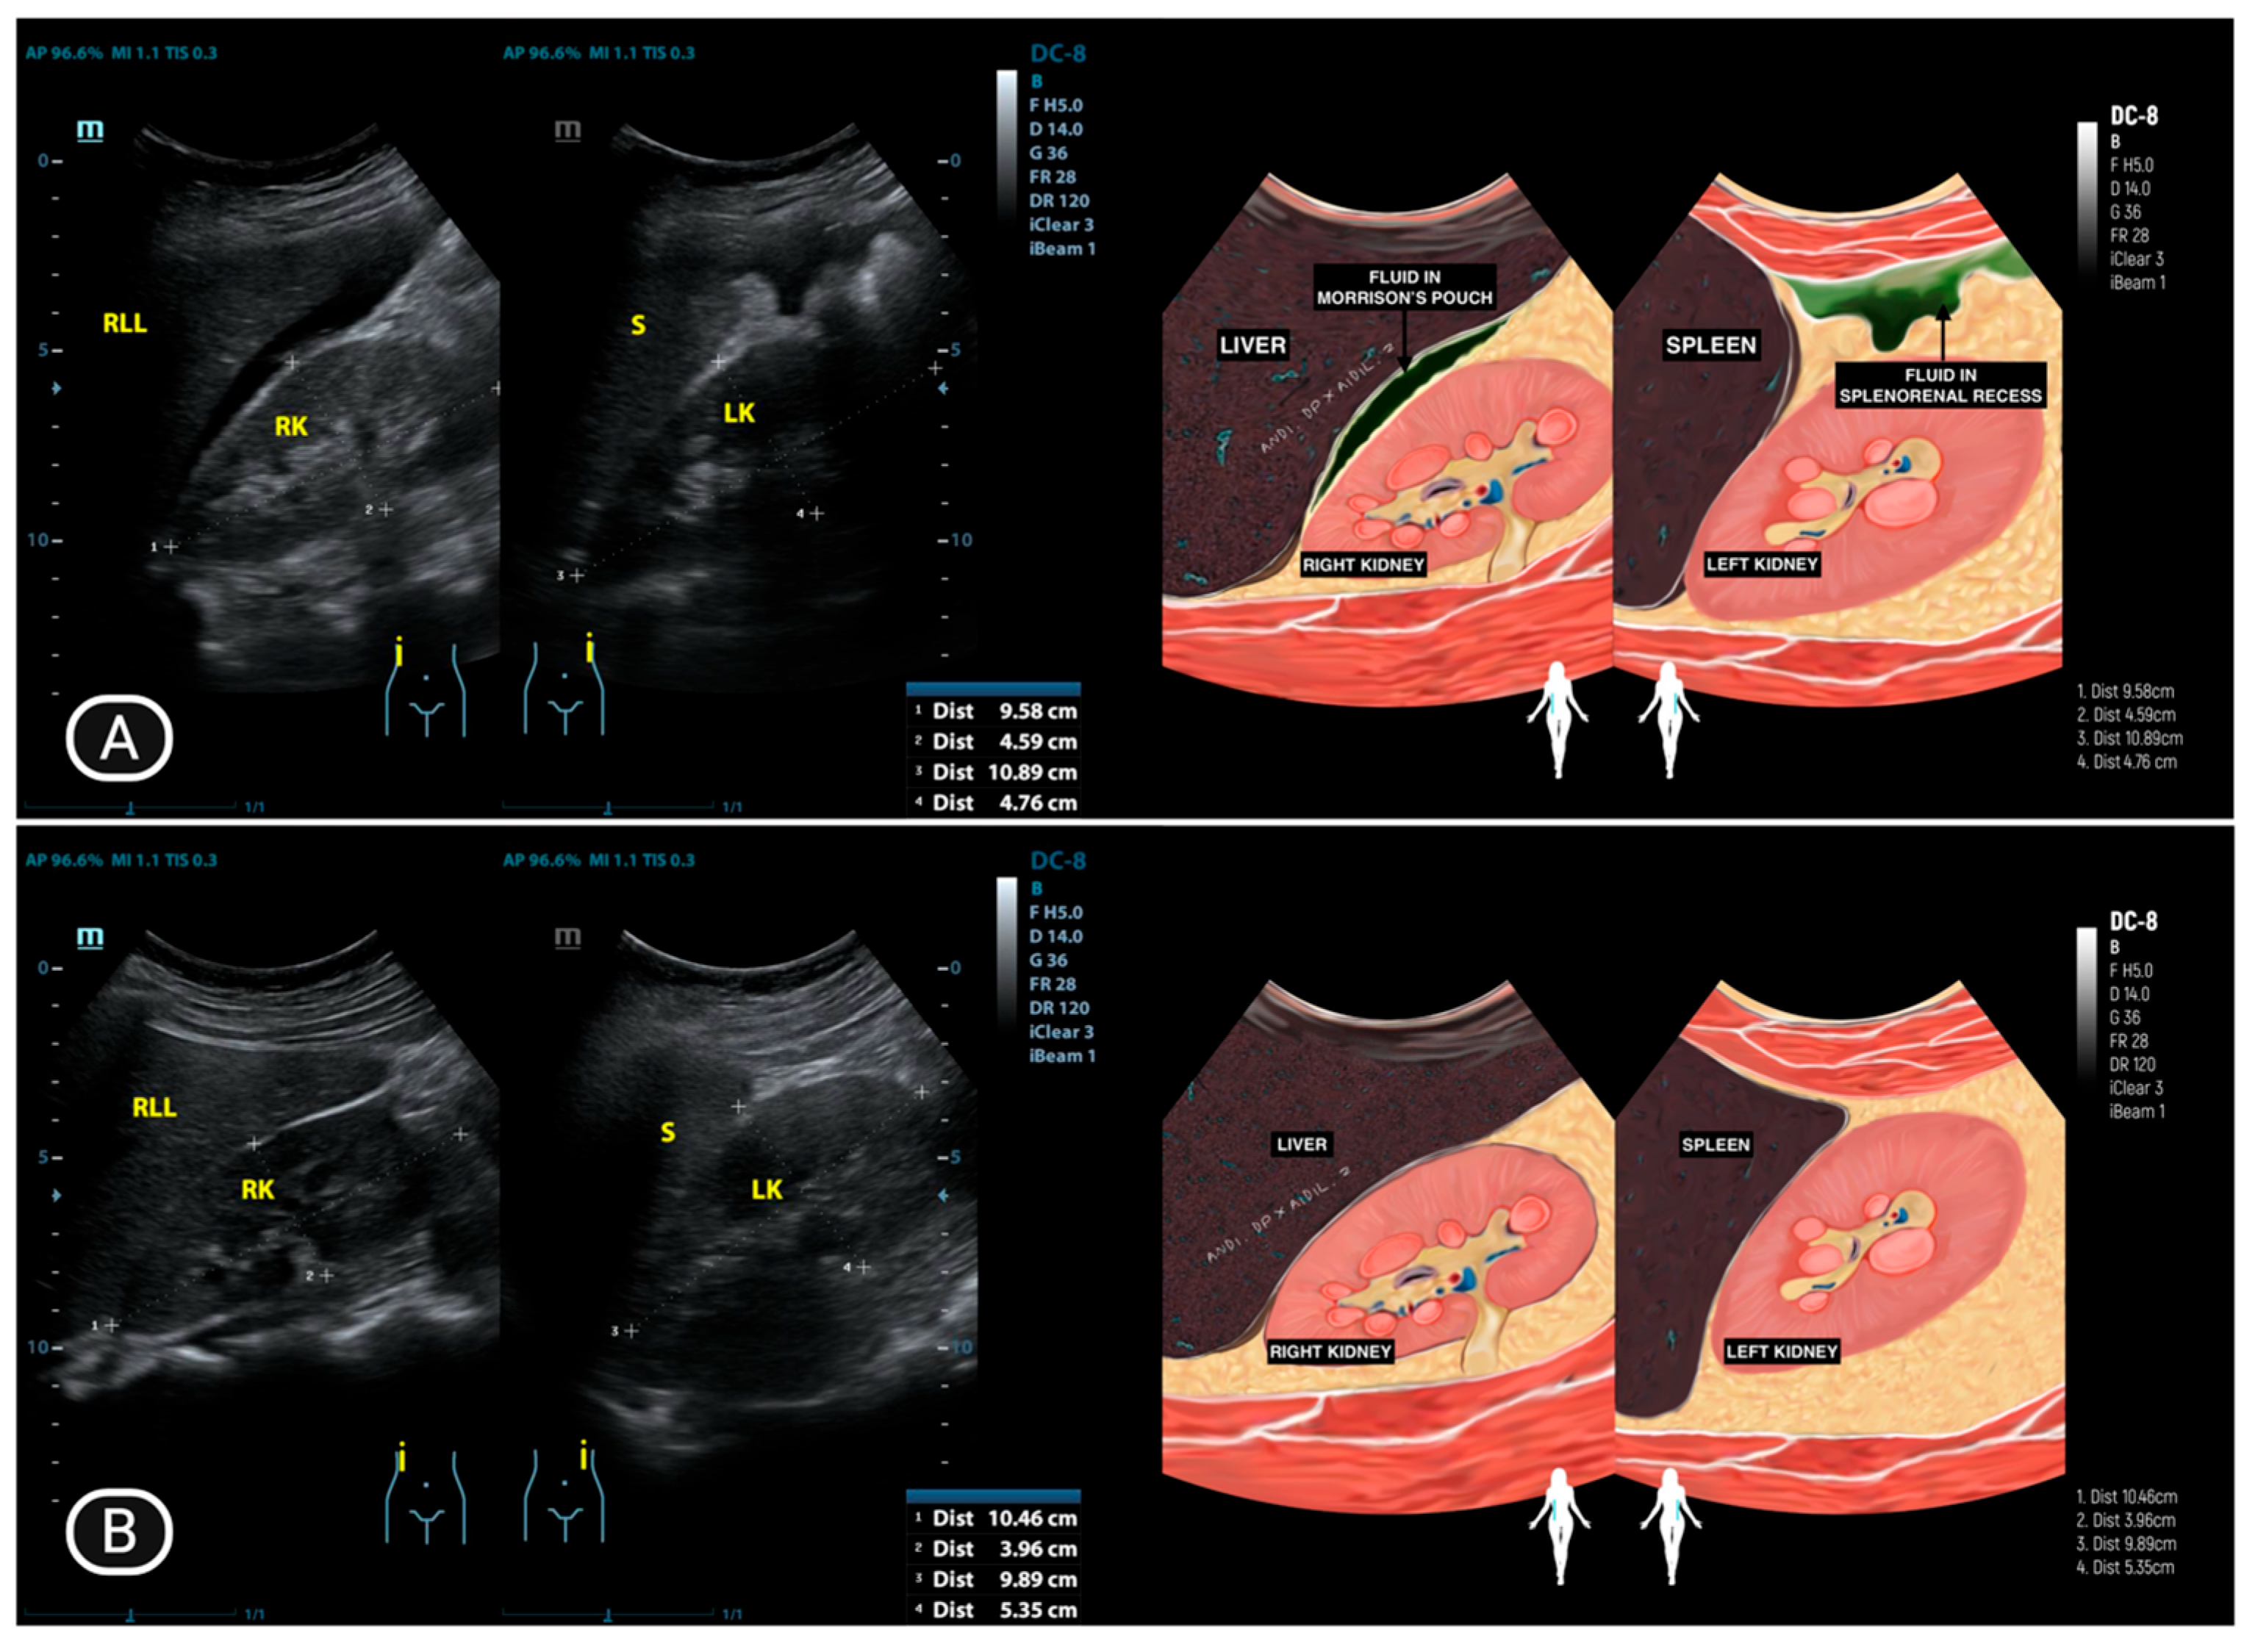

| 1 | LA (25) | Normal | Adhesion complex with hydrosalpinx right fallopian tube | Hydrosalpinx, filled with caseous degeneration inside | Adhesion complex with hydrosalpinx left fallopian tube | Hydrosalpinx, filled with complex fluid | Complex ascites | (−) |

| 2 | AY (33) | Normal | Normal | Normal | Normal | Occlusion | Free ascites | (−) |

| 5 | TDW (45) | Normal | Normal | Not visualized | Normal | Normal | Free ascites | (−) |

| 8 | OO (16) | Normal | Normal | Not visualized | Normal | Not visualized | Pocket Abscess | (−) |

| 9 | IHS (44) | Normal | Enlarged, cystic, unilocular, and contains simple fluid | Not visualized | Normal | Not visualized | Massive ascites | (−) |